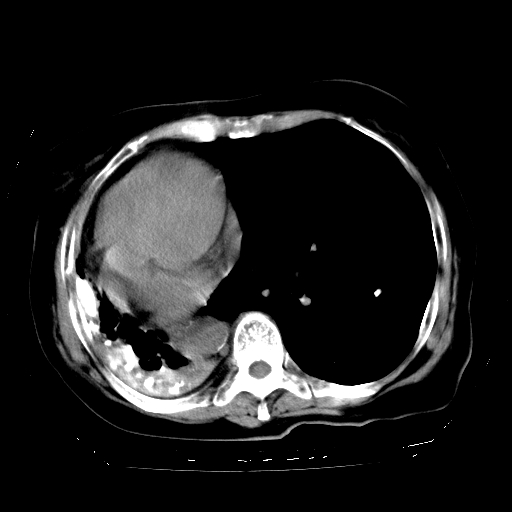

标题: CT23991:女,72岁,咳嗽、憋气一周。 [打印本页]

女,72岁,咳嗽、憋气一周,十年前曾患肺结核及胸膜结核。

右侧毁损肺,右侧纵隔疝

右侧毁损肺并纵隔疝

1.右侧损毁肺伴胸膜钙化,2.左肺小结节灶,良性可能大,注意复查。3.肝脏左叶囊肿。4.先天性一侧肺不发育待出外(右侧胸廓无明显塌陷)。对比原片应该非常有帮助。